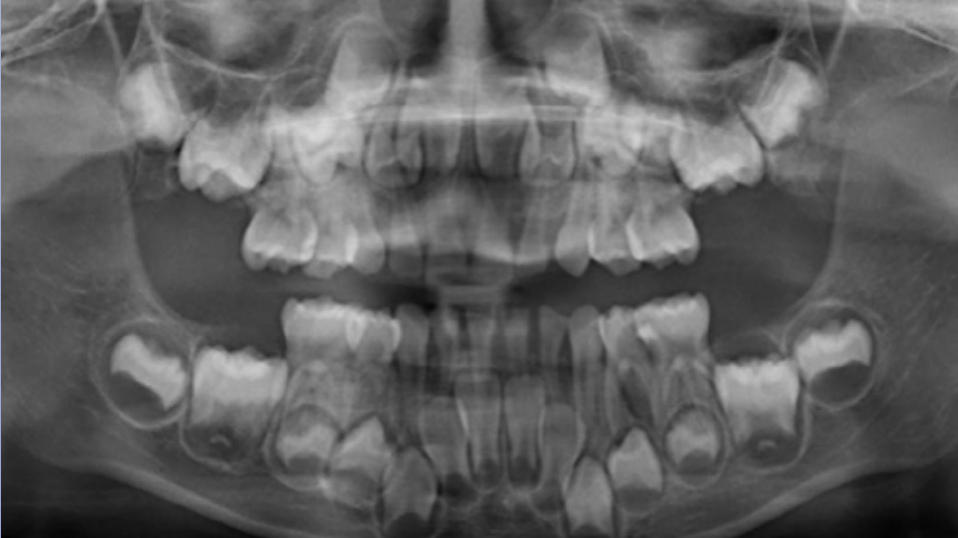

The age in this picture can be estimated by the erupted teeth which are: Maxilla ABCDE, Mandible ABCDE. The unerupted teeth are the Maxilla 1234567 and, Mandible 1234567 and the main identifying feature is the Second molar – Maxilla- 2/3 Crown completed, Mandible- 2/3 crown completed